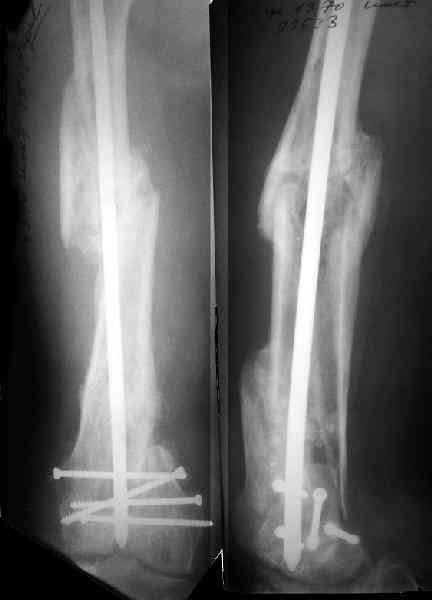

Антеградный остеосинтез при дистальных переломах бедра мы применяем давно, этот материал обобщен в канд. диссертации Александра Виноградского.

Большеберцовые стержни отлично выполняют роль ретроградных бедренных. Конечно, которые не 9, а 12 мм в диаметре.

Примеры приложены.

Принципиальности особой нет. Есть, как Д.Кулджанов упомянул, вообще гвозди одинаковые для бедра и голени. SIGN, к примеру.

Есть ретроградные с суперспециальными возможностями типа стягивающих болтов, резьбовых отверстий, клинков. Гвозди Stryker, безусловно, очень хорошие. Однако бОльшая часть переломов успешно может быть фиксирована более простыми и универсальными имплантатами. Теми же большеберцовыми, к примеру. Если надо, плюс 1-2 спонгиозных винта мимо гвоздя. Хотя вообще для самых дистальных переломов мы предпочитаем антеградное введение.

Затем, что результаты как минимум не хуже, чем при использовании глубокоспециализированных DFN. Другое дело, что найти толстый тибиальный гвоздь больше 11м не всегда просто. В показаном примере он бы не подошел. Трочал бы сильнее из колена или при полном погружении отверстия пролетели бы проксимальнее перелома. Он показан больше для нижней трети, чем для области метафиза. Да и желательно чтобы винты толстые были, толще чем для тибии.

2. Лучше борется с рекурвацией дистального отломка за счет угла Герцога.(В представленном примере "недопобороли")

В данном случае, на мой взгляд, если говорить о гвоздях, предпочтительней антеградное штифтование. Поскольку любая ретроградная конструкция не может иметь столь низкого расположения отверстий для винтов как антеградная из-за резьбового крепления.

Это результат через полгода. К сожалению, пациент больше не приезжал на контрольный осмотр.